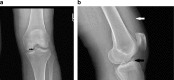

Tibial eminence avulsion fractures are not infrequent in the pediatric population; however, they are rare in the adult population. These injuries typically occur in skeletally immature patients between the ages of 8 and 14 years. We report the unique clinical history, imaging findings, and operative results of a 48-year-old female who presented with severe knee pain. Imaging findings revealed an anterior tibial eminence fracture with an intact anterior cruciate ligament tendon attached to the avulsed fragment. The patient underwent knee arthroscopy, with direct repair of the tibial eminence fracture.